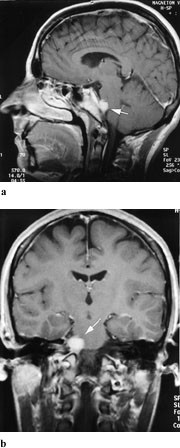

Fasikulær lesjon i hjernestammen er hyppig, og alltid assosiert med andre utfall, som hemiparese, hemitremor eller cerebellar ataksi, avhengig av hvilke andre strukturer som skades samtidig (tab 2) (1). Påvisning av patologisk tilstand, både ved kjerneområdet og i hjernestammen, som kan være betinget i blødning, infarkt, tumor, demyelinisering eller arteriovenøs malformasjon, gjøres best med MR (2), (fig 1a, b). Hjernestammen fremstilles dårlig med CT pga. artefakter fra omgivende bein, og CT bør kun anvendes i tilfeller hvor MR-undersøkelse er kontraindisert (pacemaker, ikke magnetkompatible klips, klaustrofobi). Oculomotoriusnerven i cisternerommet kan påvirkes av aneurisme (a. carotis interna eller a. communicans posterior). Dette er årsaken til parese i hjernenerve III hos en tredel av pasientene (3), og hos de aller fleste starter det med kraftig hodepine. Dilatasjon av pupillen er i slike tilfeller nesten obligatorisk funn, siden pupillens motorfibrer er beliggende overflatisk i nerven i dette området og er meget vulnerable for trykk. I mindre enn 5 % av tilfellene er pupillen ikke affisert. Man kan ikke utelukke aneurisme selv om hodepinen mangler. Aneurismer kan debutere med subaraknoidalblødning. CT uten kontrast er den beste metoden for å vise blod i subaraknoidalrommet (4). CT-angiografi er vårt første valg for å fremstille aneurismer (fig 2a, b), men metoden krever injeksjon av kontrastmiddel (5). Ved sterk klinisk mistanke og negativ CT-angiografi bør konvensjonell angiografi utføres.

Langsomt progredierende oculomotoriusparese med pupillaffeksjon kan være forårsaket av nevrinom, som er isointens på T1- og T2-vektede MR-bilder og viser kraftig signalopptak etter intravenøs injeksjon av gadoliniumkontrast (fig 3).